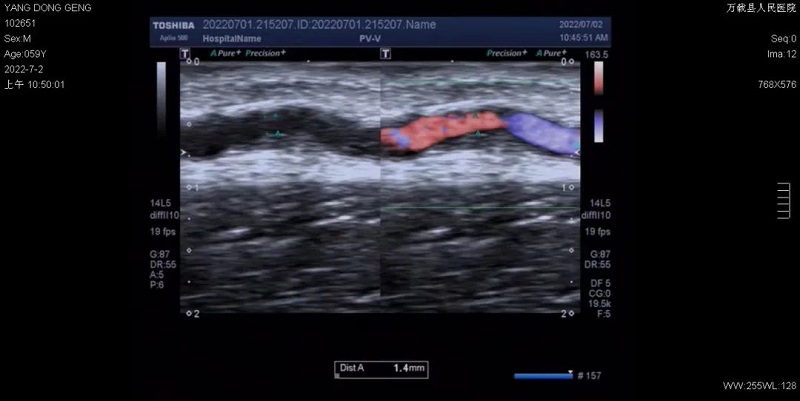

万载县人民医院肾内科,自2009年开展血管通路手术以来,完成各种复杂通路手术已超二千余例。为更好地做到血管通路规范化管理,2021年 8 月,万载县人民医院肾内科开设血管通路门诊,门诊设置于血液净化室医护办公室,成立血管通路多学科诊疗(MDT)团队,团队中配有肾内科医师、血管通路手术医师、超声科医师、血透穿刺护士。血管通路MDT团队对慢性肾脏病3-5期患者进行从上肢血管保护、通路规划、术前评估、手术、术后随访、内瘘监测、内瘘使用与护理到并发症处理等全周期管理;为患者现场进行彩超检查血管通路,及时准确提供诊断和治疗意见;血透穿刺护士现场参与,更多角度地为透析患者提供血管通路穿刺及维护建议。全方位闭环式的监测及管理能为患者的血管通路提供有力保障。

我院血管通路门诊开设11个月以来,就诊患者数已超一千人次,完成血管通路日间手术10例,完成超声/DSA下经皮血管腔内成形术、DSA下疑难血透导管置入术、动静脉内瘘修复术、PTA+血管补片杂交手术等复杂手术100余例。手术效果显著,患者均满意出院。相信我们的不断创新、努力,能为更多透析患者带来福祉。